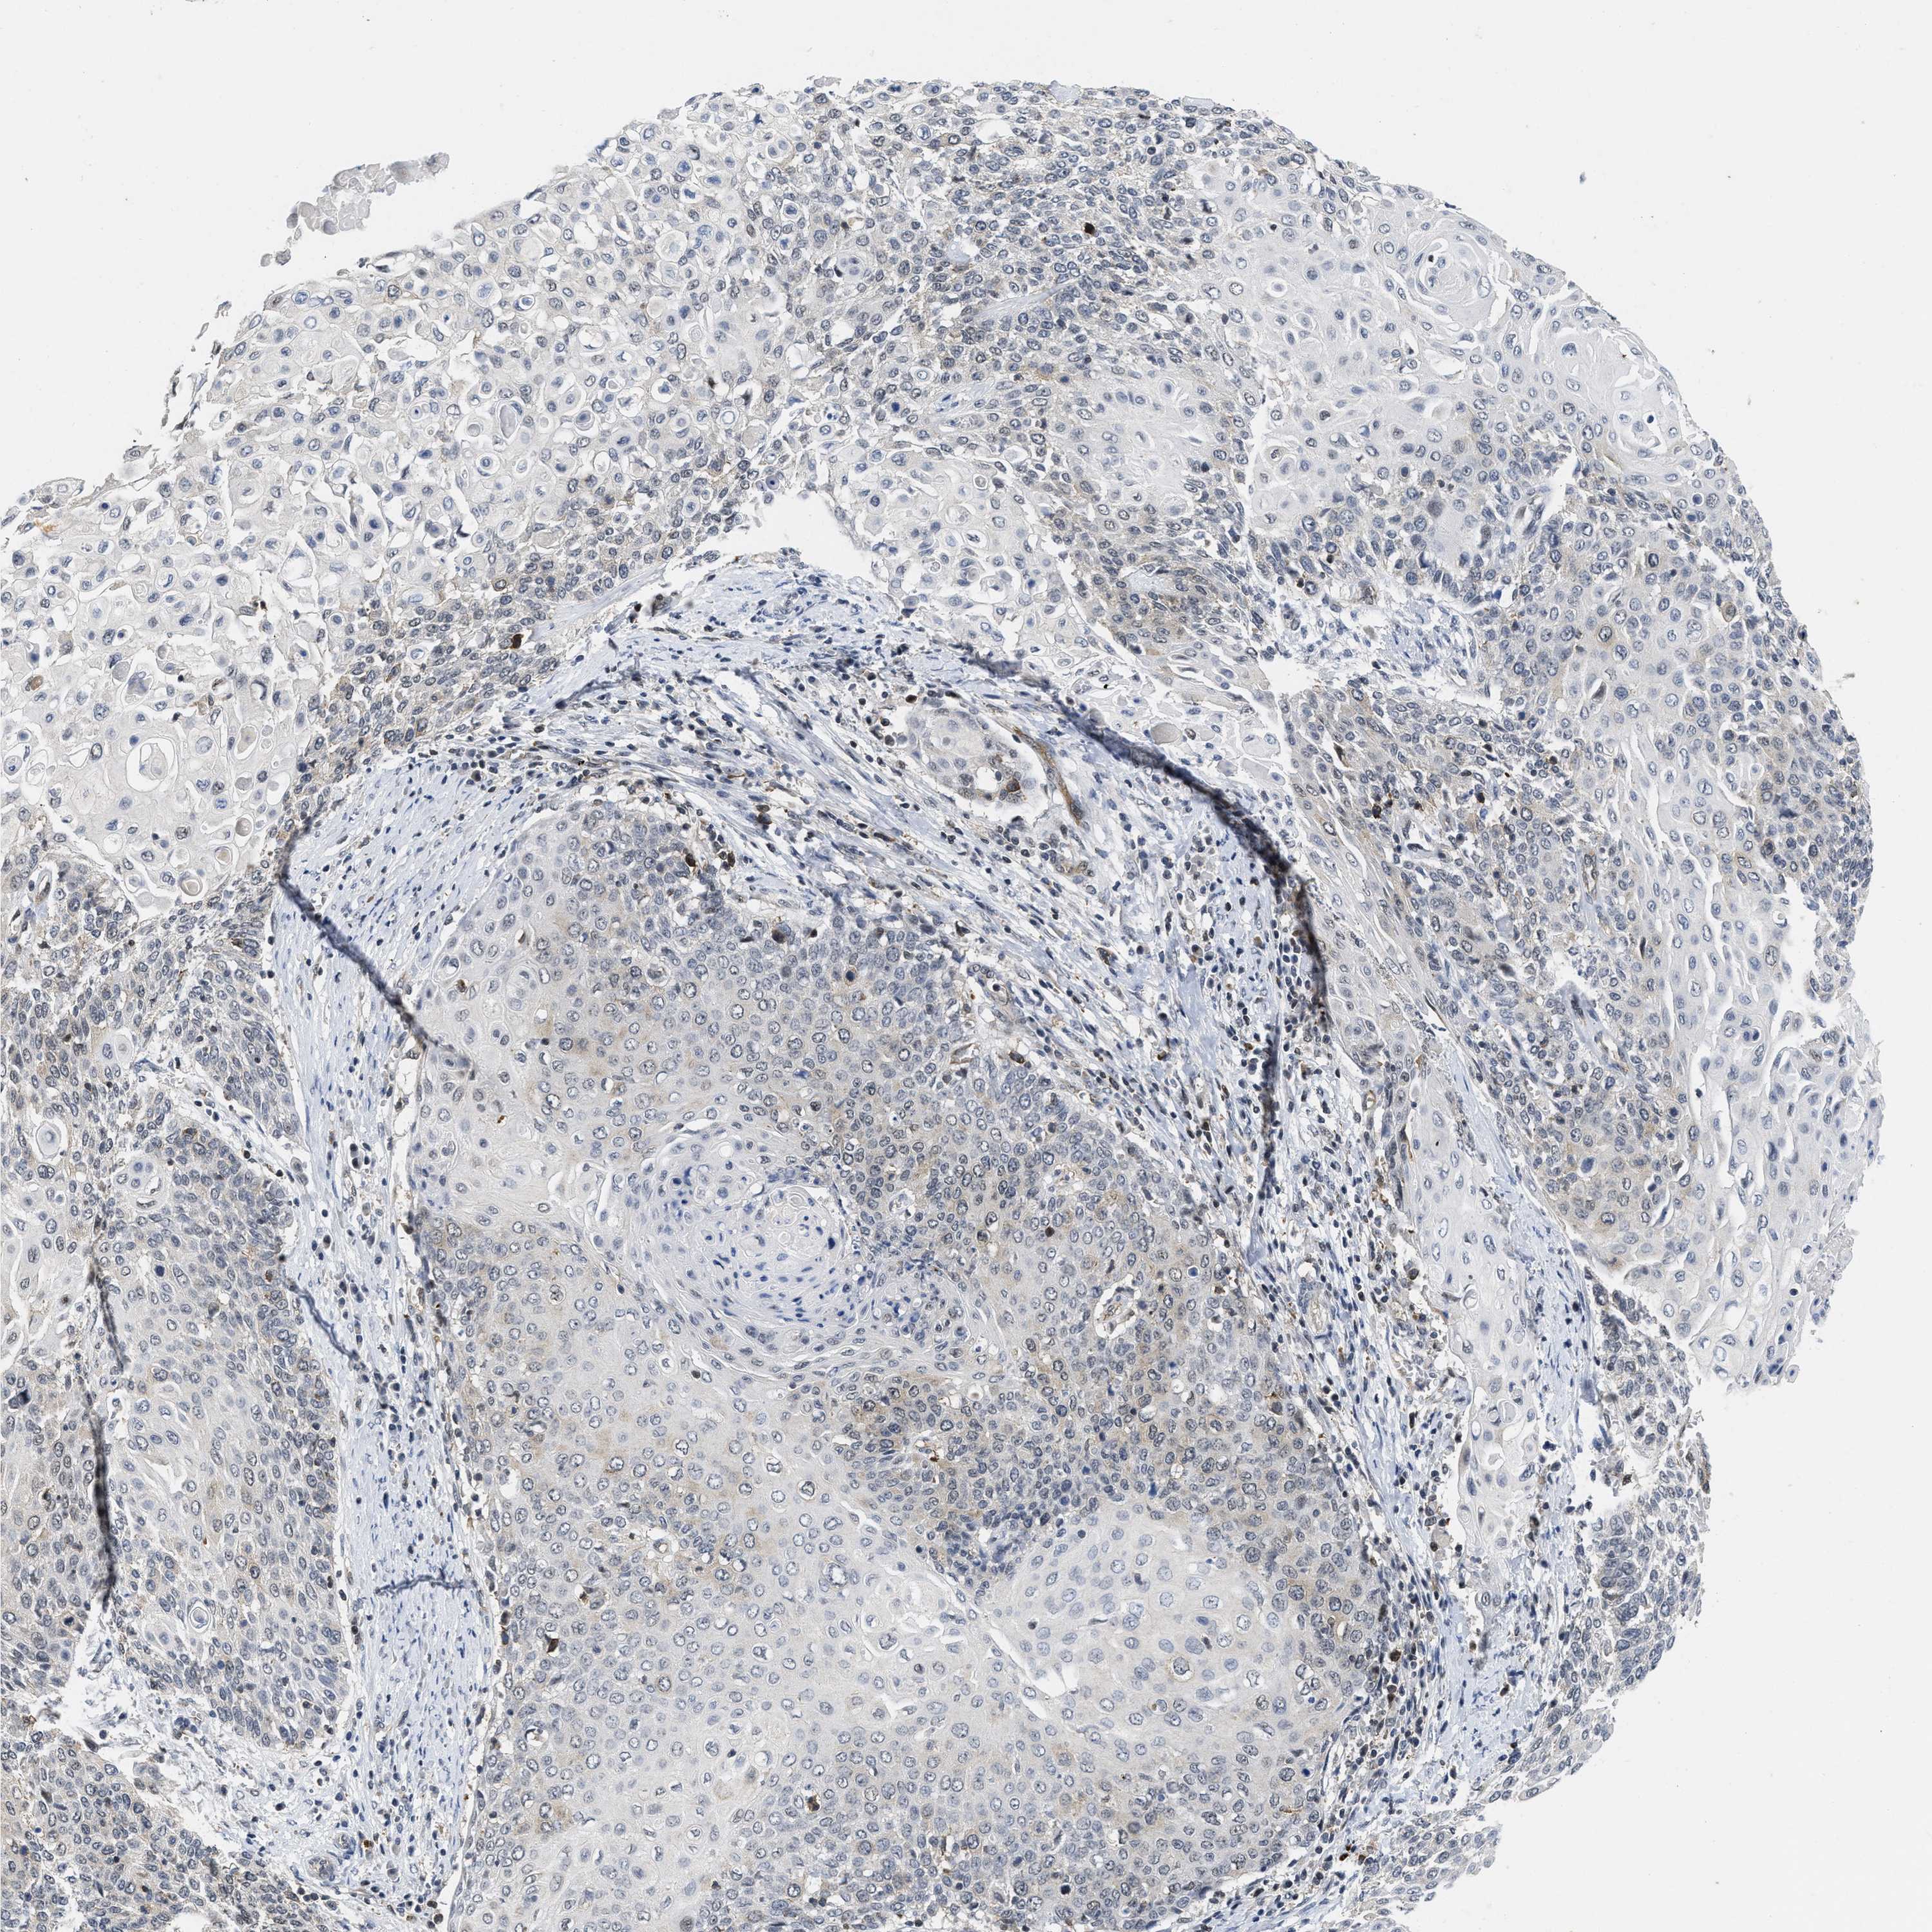

CERVICAL CANCER - Protein expressioni

A mouse-over function shows sample information and annotation data. Click on an image to view it in a full screen mode. Samples can be filtered based on level of antibody staining by selecting one or several of the following categories: high, medium, low and not detected. The assay and annotation is described here.

Note that samples used for immunohistochemistry by the Human Protein Atlas do not correspond to samples in the TCGA dataset.

Antibody stainingi

Antibody staining in the annotated cell types in the current human tissue is reported as not detected, low, medium, or high, based on conventional immunohistochemistry profiling in selected tissues. This score is based on the combination of the staining intensity and fraction of stained cells.

Each image is clickable and will lead to virtual microscopy that enables deeper exploration of all samples and also displays staining intensity scores, fraction scores and subcellular localization as well as patient and tissue information for each sample.

Antibody HPA001275

Antibody CAB017442

Staining

High

Medium

Low

Not detected

Intensity

Strong

Moderate

Weak

Negative

Quantity

>75%

75%-25%

<25%

None

Location

Nuclear

Cytoplasmic/membranous

Cytoplasmic/membranous,nuclear

Adenocarcinoma, NOS